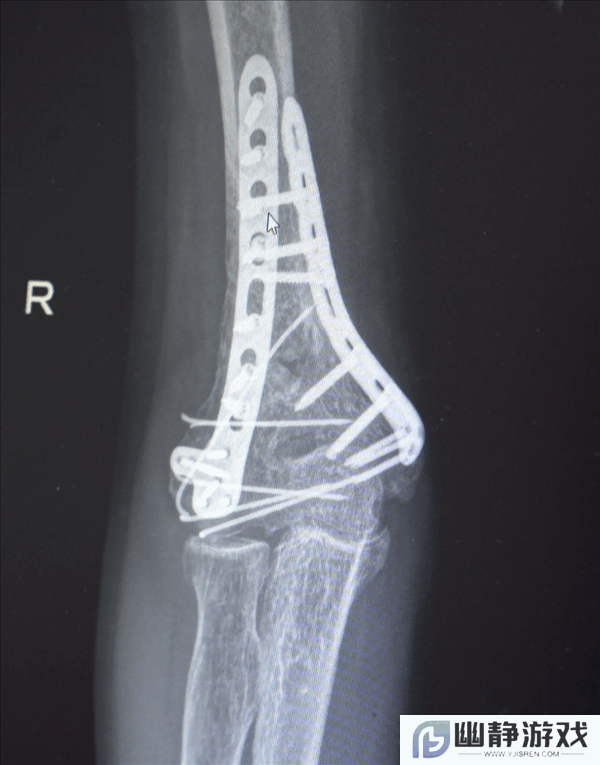

鉴于男子多处骨折,其中最严重的当属右肘部C3型粉碎性骨折,关节面及髁上严重粉碎(碎成了七块),肘关节易粘连,复位固定难度极高。

最终医疗团队采用了“拼古董”式复位固定技术,就像修复一件珍贵的古董瓷器,先拼接大块骨块再贴合小块,先后进行了两次手术。